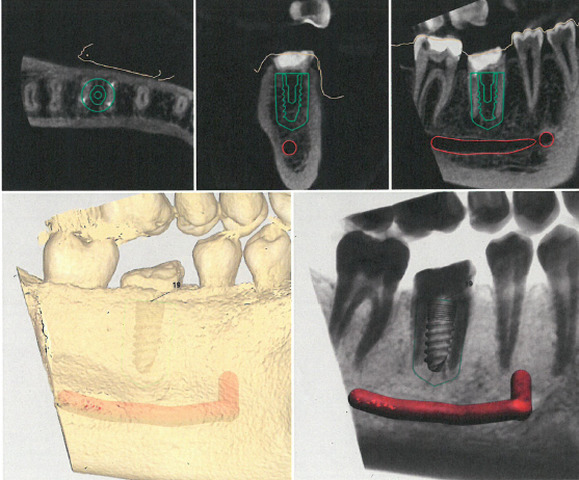

Ryc. 1. Stan kliniczny zęba 36.

Wykonano pantomogram oraz zdjęcie celowane, które ujawniło zmianę okołowierzchołkową przy korzeniu dystalnym. Nie stwierdzono patologii tkanek twardych zębów sąsiadujących z zębem zakwalifikowanym do ekstrakcji, dlatego powzięto decyzję o odbudowie implantologicznej przyszłego braku zębowego (ryc. 1-3).

Ryc. 2. Zdjęcie pantomograficzne wykonane przed zabiegiem. Ryc. 3. Zdjęcie zębowe zęba 36.